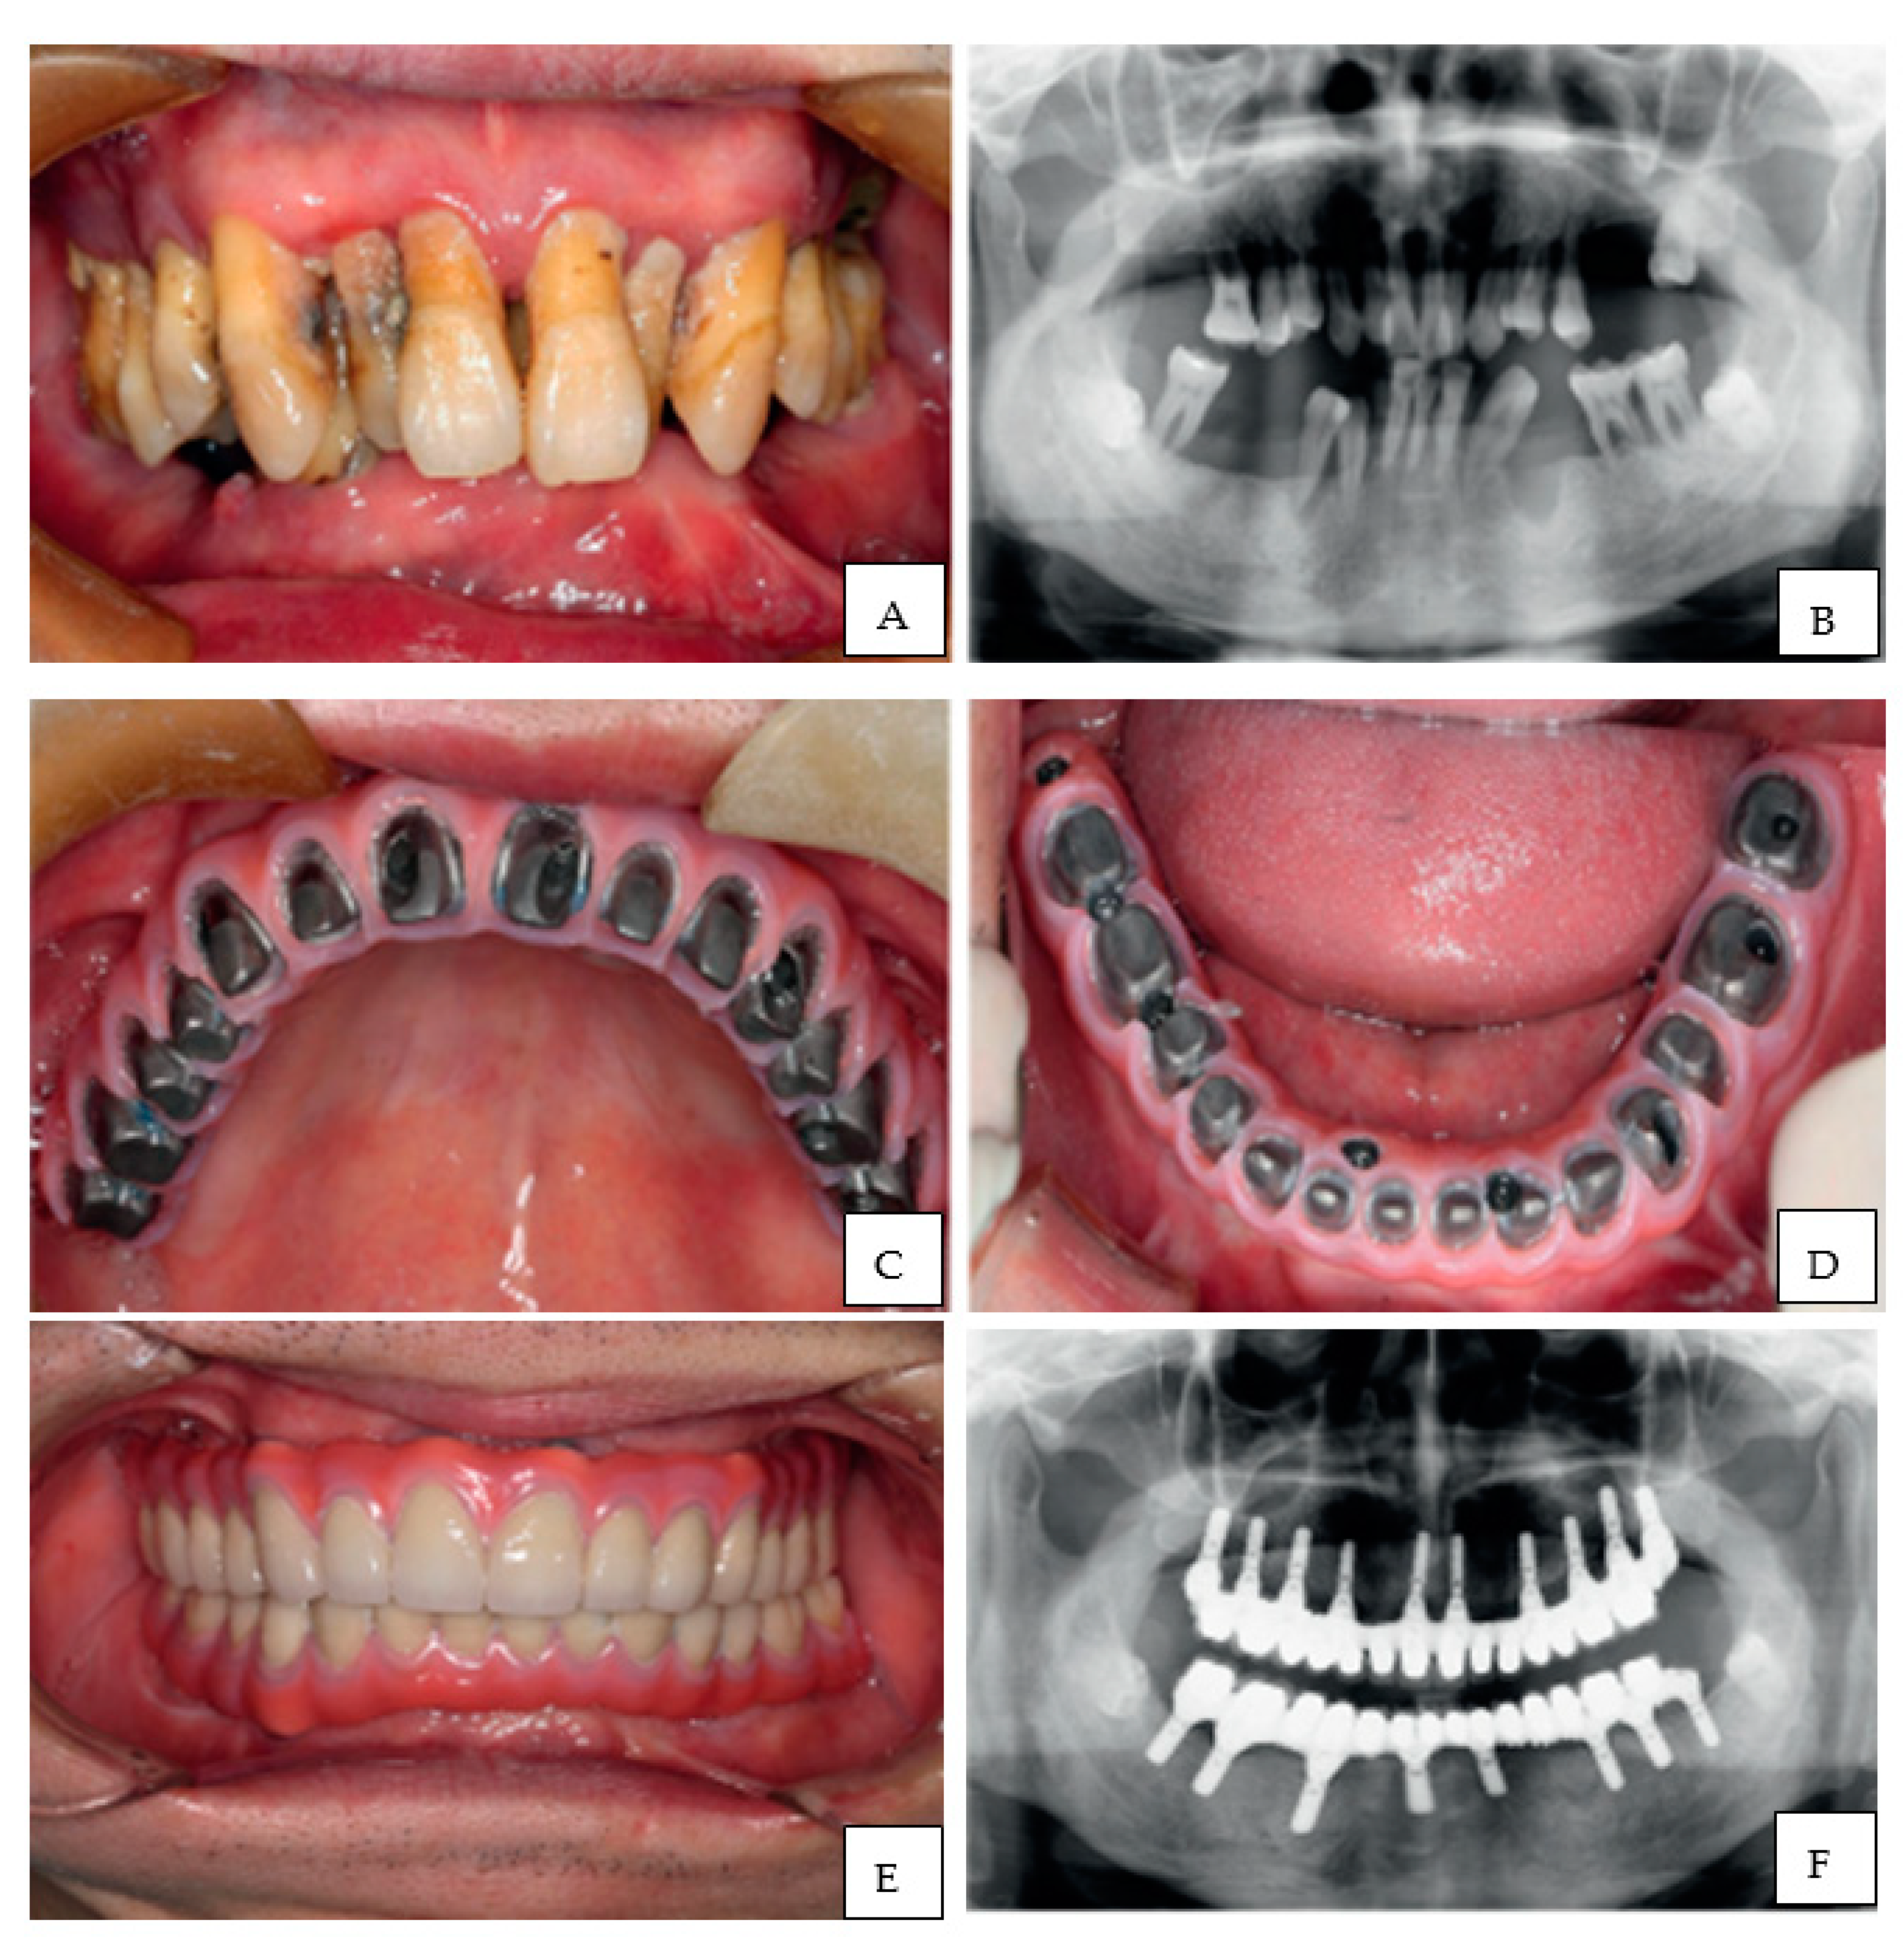

An impressive example of full mouth restoration using CAD/CAM technology in a patient with severe periodontitis and alveolar ridge atrophy is described by Wang et al. (2018) (Figure 4). They restored the atrophic arches by fabrication of 3D printed customized titanium framework over which implants were supported, leading to restoration of function as well as esthetics [119].

Figure 4.

(A) Pre-operative condition- Intra-oral, (B) Panoramic radiograph, (C,D) Screw retained framework, maxillary and mandibular respectively, (E) Intraoral view of definitive prosthesis in place, (F) Panoramic radiograph after treatment. Images re-printed with permission from Wang et al. [119].